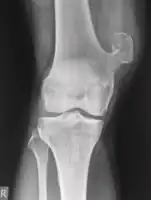

Medical imaging usually shows a well-defined wide-based bony growth on the surface of bone.[5] It can be pedunculated and irregular, giving it a "bizarre" appearance, and is not connected to underlying bone.[2]

X-ray left foot: Bizarre parosteal osteochondromatous proliferation in 2nd toe -